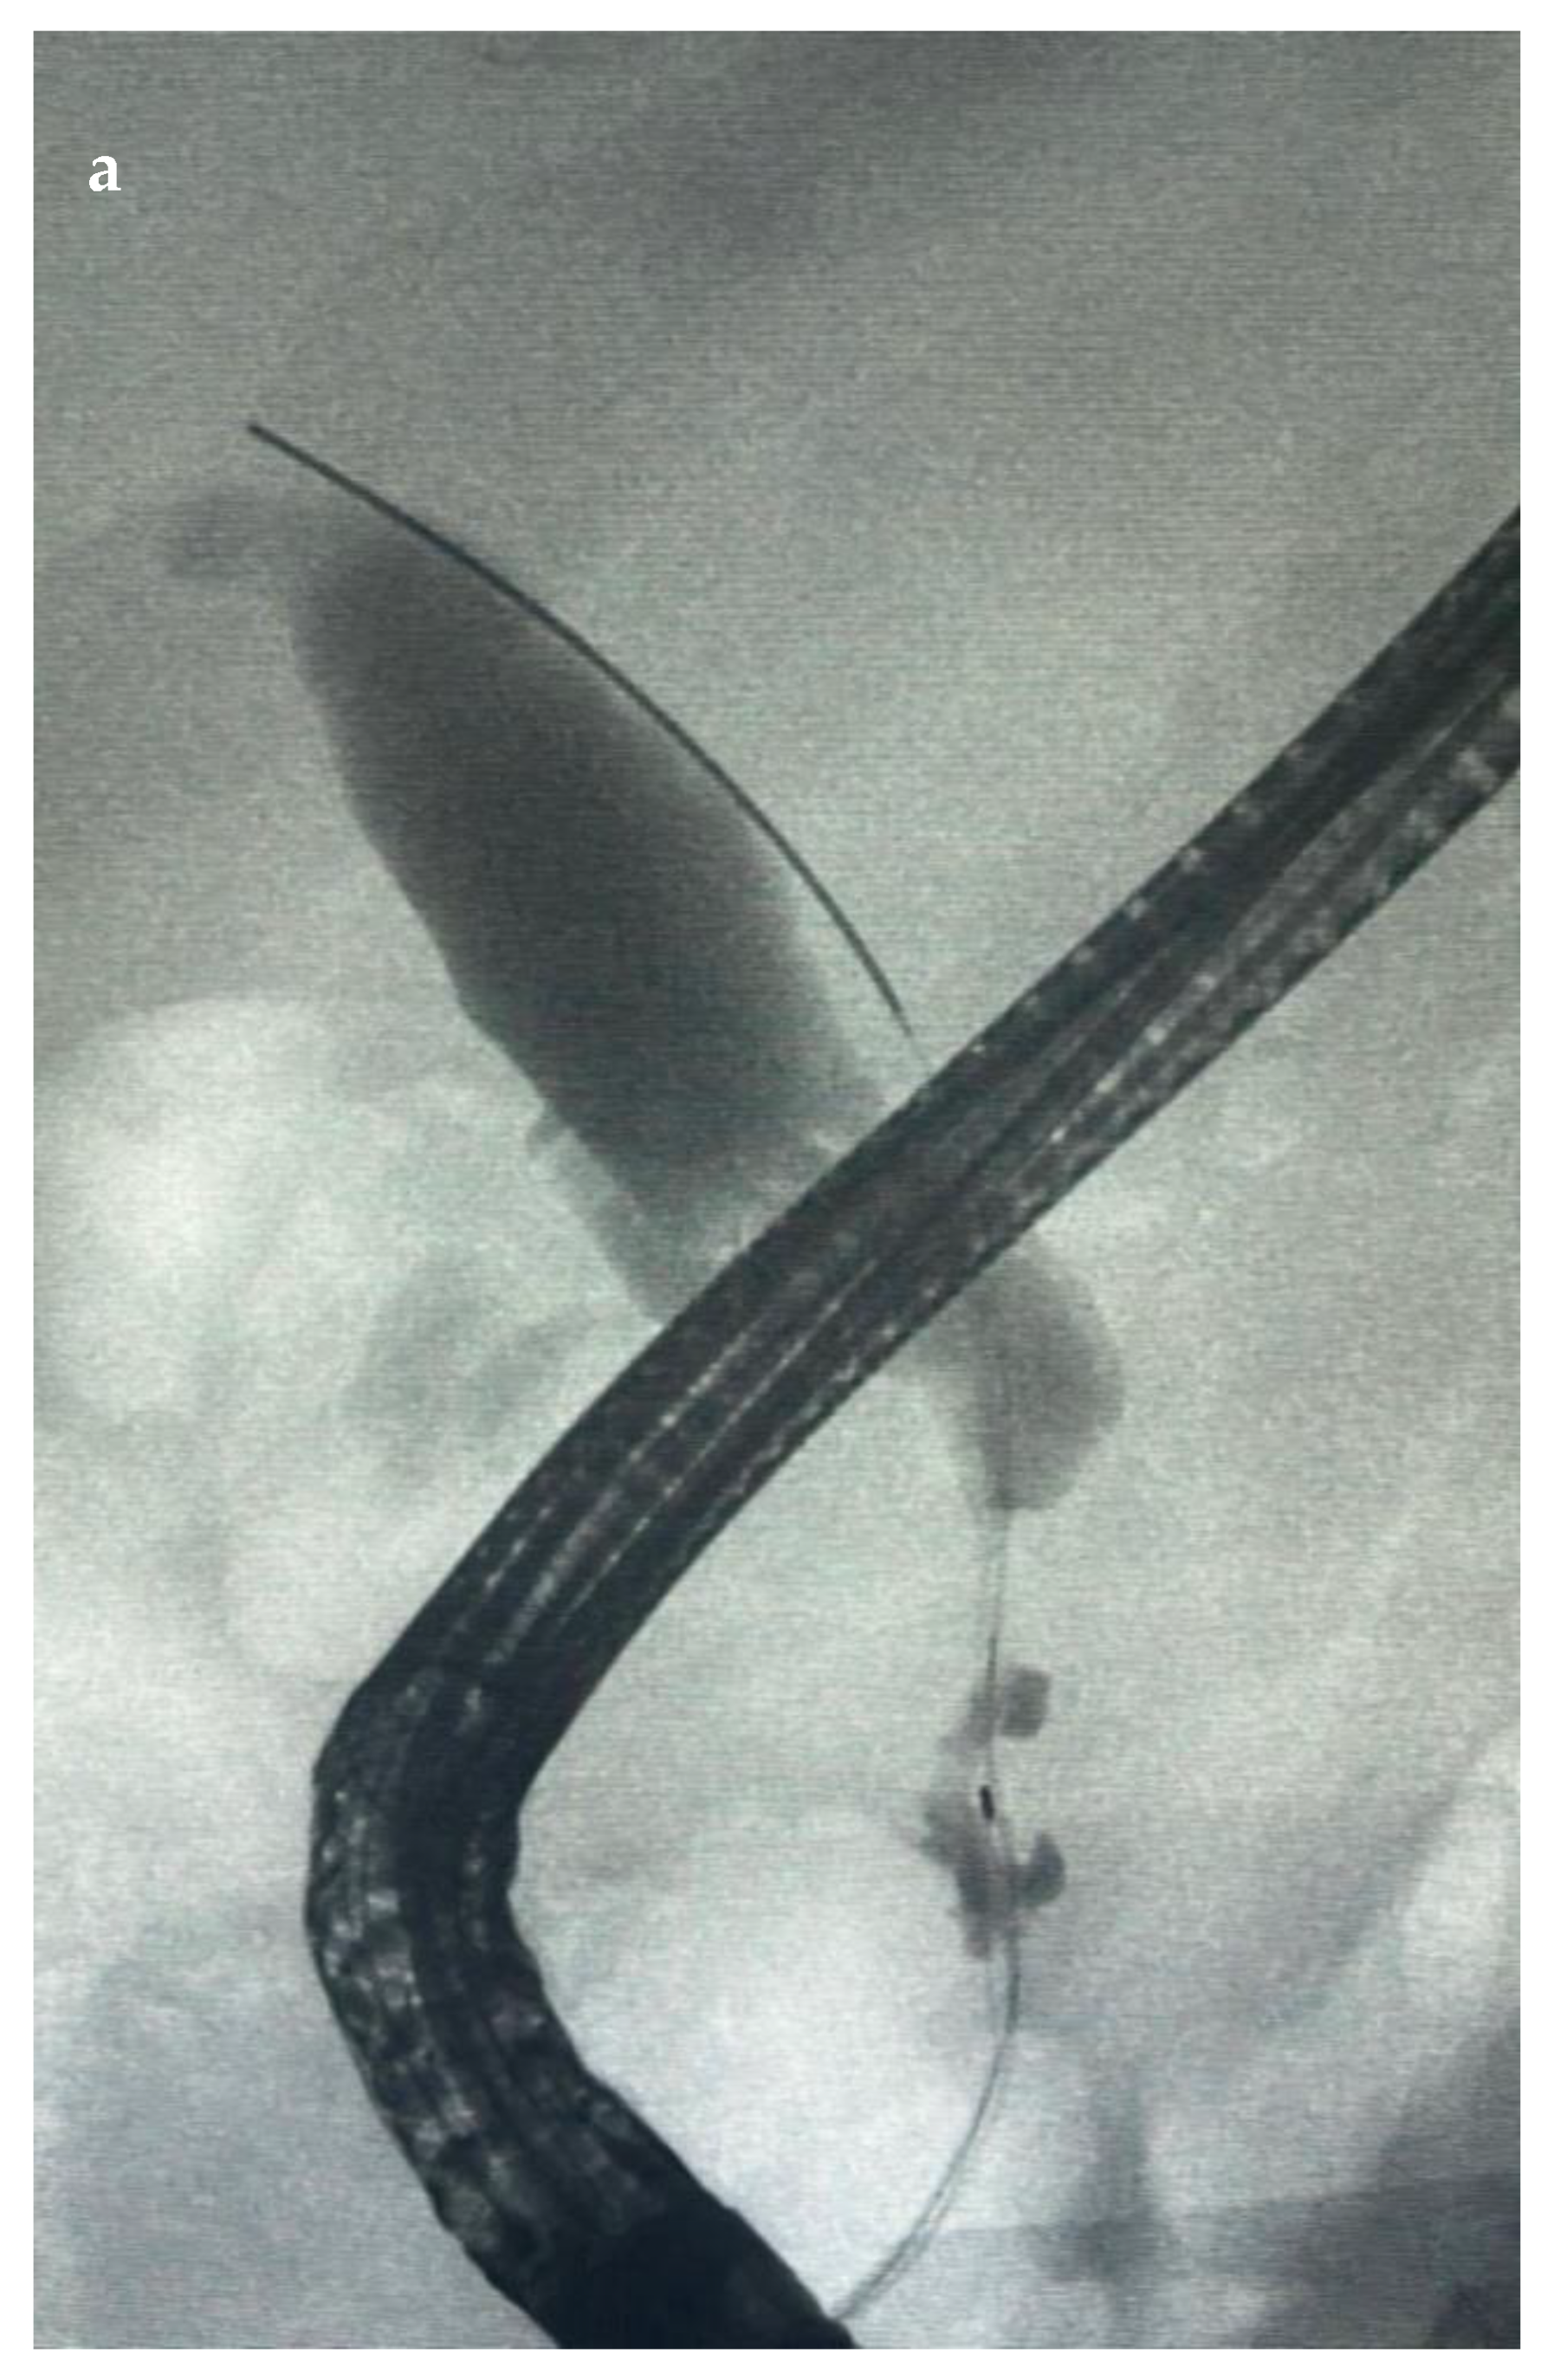

6.4.2. Endoscopic Retrograde Cholangiopancreatography (ERCP)

7.1.3. EUS-Guided Biliary Drainage (EUS-BD)